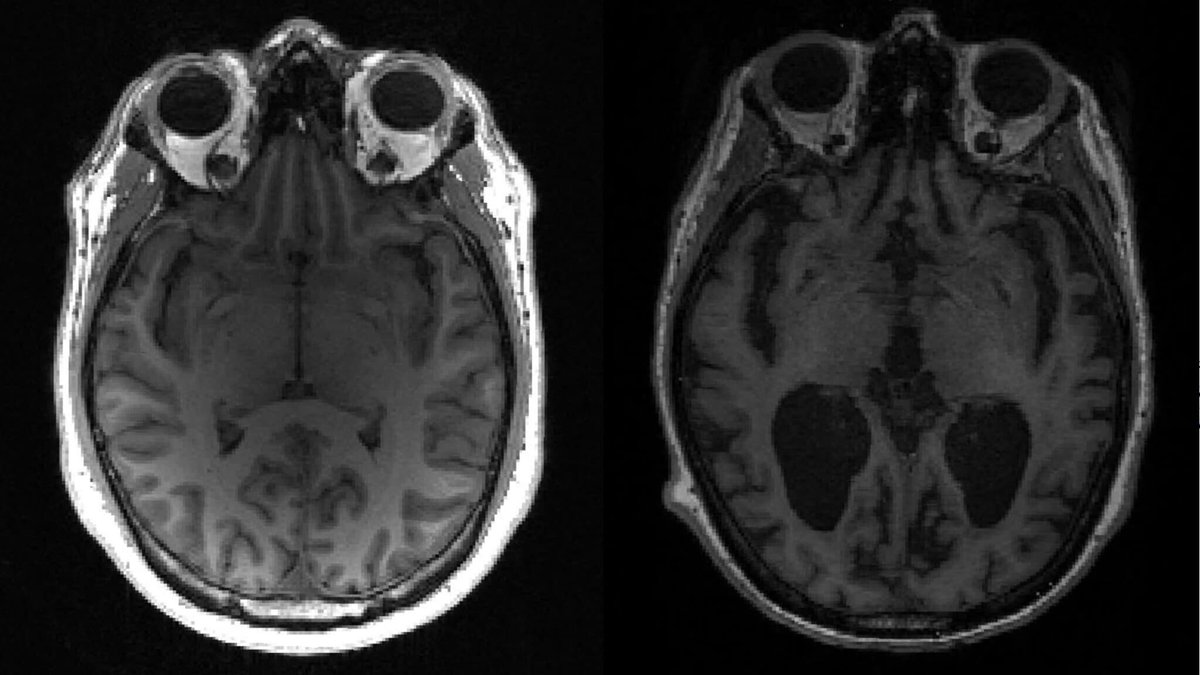

Une découverte "inattendue" et "inespérée": un nouveau mécanisme de la maladie d'Alzheimer identifié par des chercheurs français l.bfmtv.com/37jN

Une découverte "inattendue" et "inespérée": un nouveau mécanisme de la maladie d'Alzheimer identifié par des chercheurs français